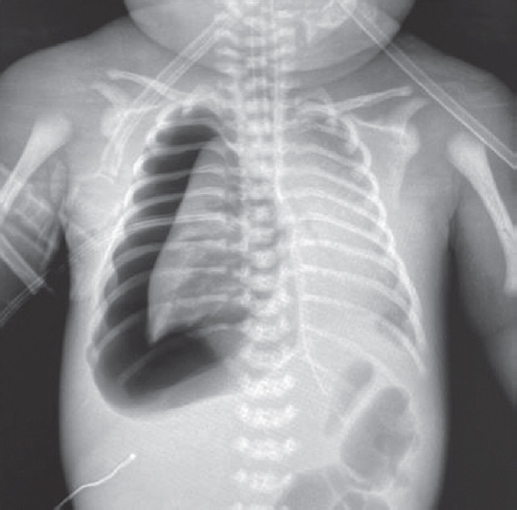

The article presents a case of successful treatment of acute respiratory distress syndrome in a full-term newborn complicated by pulmonary barotrauma using monobronchial administration of exogenous surfactant under X-ray control. In order to assess the course of the disease and the effectiveness of treatment, a retrospective analysis of medical documentation was carried out. From the first minutes of life, the child had respiratory disorders, which was the basis for non-invasive mechanical lung ventilation — nCPAP (nasal continuous positive airway pressure). Progression of hypercapnia and hypoxemia was revealed over time, and therefore tracheal intubation was performed and convective mechanical ventilation was started with FiO2 = 1,0. Monobronchial administration of exogenous surfactant was a key element of the therapy that allowed to achieve stabilization of the condition and regression of gas exchange disorders with complete recovery of the patient.